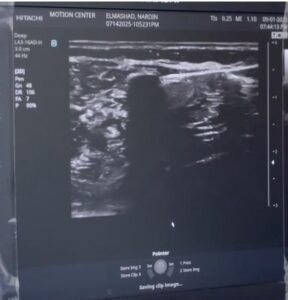

الاستعانة بتقنية الموجات فوق الصوتية لضمان دقة الاستهداف.